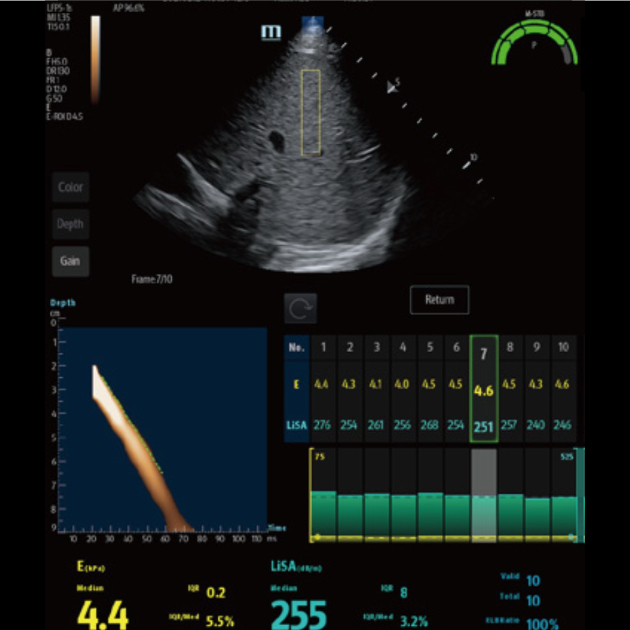

? ??? ?? ???? ???? ?? ???? Hepatus? ? ??? ??? ???? ??? ??? ?????. ???? ????? ??? ? ?? ??? ???? ????? ? ?? ???? ? ?? ??? ??? ??? ?????.

??? ???? ?? ? ??? ? ? ???? ?? ??, ??, ???? ? ?? ??? ??? ? ????. ?? ?? ???? ?????.